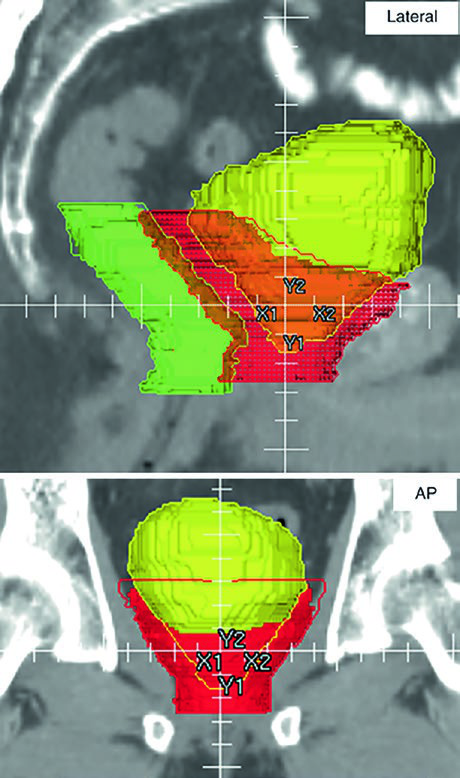

A Fig. 25.5 mostra um caso particularmente didático: paciente com doença linfonodal regional, T1cN1M0, Gleason 4 + 4 e PSA 22, tratado com IG-IMRT moderadamente hipofracionada e 2 anos de Lupron com Abiraterona. A radioterapia foi feita com dose painting em 26 frações: 4680 cGy para a pelve eletiva, 5720 cGy para o linfonodo pélvico direito grosseiro e 7020 cGy para próstata e vesículas seminais. Além da distribuição de dose, a legenda chama atenção para a RM de 3 T fundida na posição de tratamento para ajudar tanto no CTV prostático quanto na visualização do espaçador retal. É um bom lembrete de que a fusão de imagem, aqui, tem papel simultaneamente anatômico e estratégico.